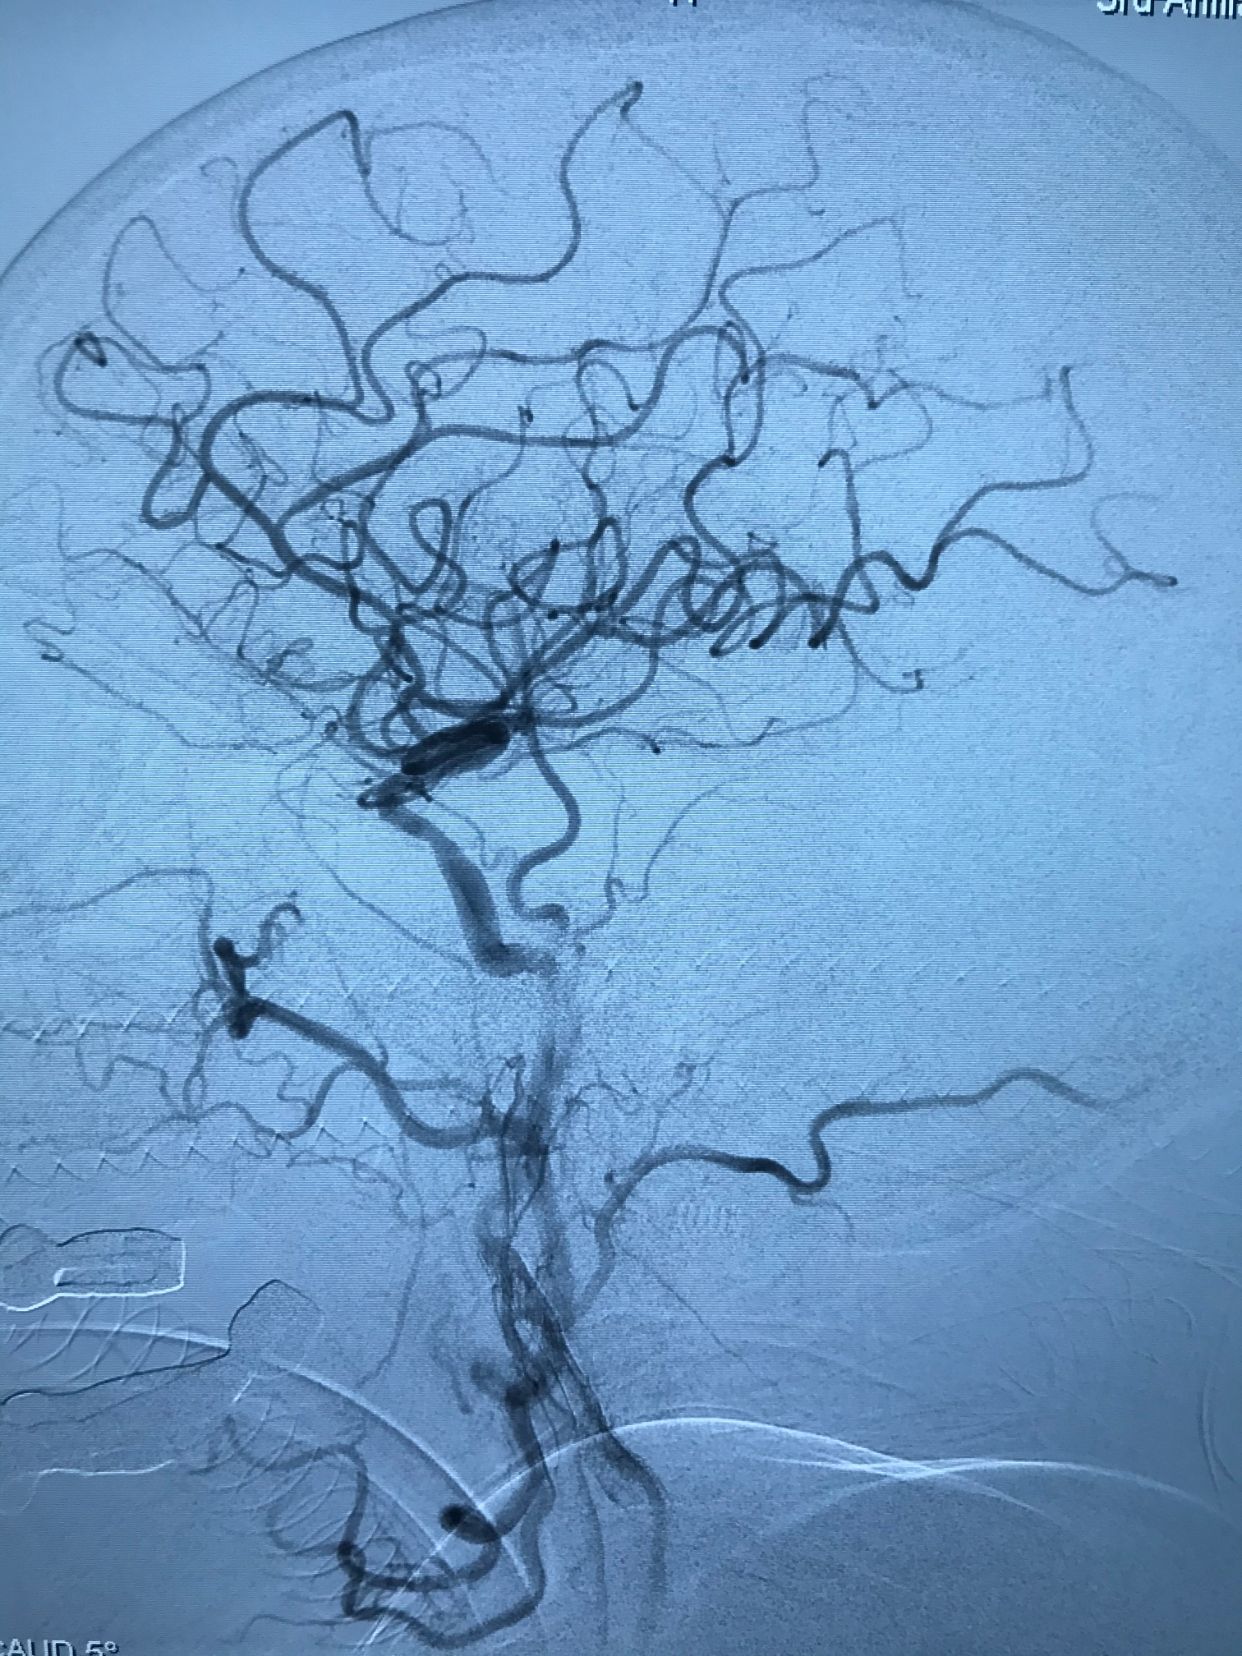

入院后先静脉溶栓,溶栓期间症状加重,右侧肌力持续下降,逐渐出现意识障碍!急诊造影显示左侧颈内动脉开口重度狭窄基础上急性闭塞!

微导丝轻松通过闭塞段,小球囊预扩!

上保护伞!

保护伞下球囊扩张支架植入!

血流恢复!

术后正位造影,颅内血管显影良好!

术后侧位造影!